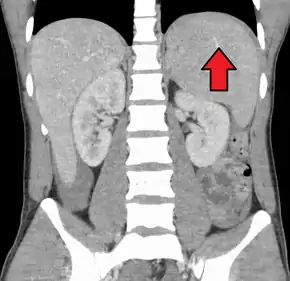

Spleen enlargement is common in the second and third weeks, although this may not be apparent on physical examination. Rarely the spleen may rupture.[23] There may also be some enlargement of the liver.[21] Jaundice occurs only occasionally.[13][24]

Splenomegaly is a common symptom of infectious mononucleosis and health care providers may consider using abdominal ultrasonography to get insight into the enlargement of a person's spleen.[54] However, because spleen size varies greatly, ultrasonography is not a valid technique for assessing spleen enlargement and should not be used in typical circumstances or to make routine decisions about fitness for playing sports.[54]